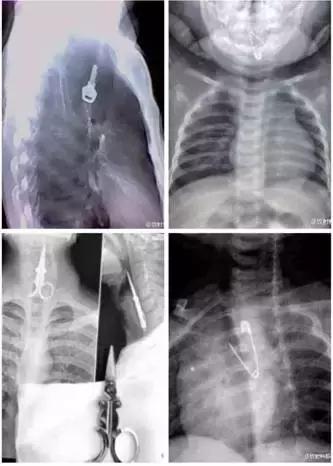

X光下的奇葩异物

食管异物多见于1~5岁幼儿,多由于将异物放入口内玩耍误吞引起,也可因饮食不慎将枣核及骨片等物吞入。最常见的消化道异物为枣核、骨片、硬币、徽章、纽扣、别针、螺钉等。小编见过比较别致的异物有:牙刷、玻璃片、半把梳子等等。好奇是孩子的天性,而处于口欲期的孩子通常都是通过啃、咬物体对其进行感知。所以家长就要加强对孩子的看护,避免吞入异物。

我们生活中遇到的“误吞”,除了枣核,常见的还有鱼刺、假牙、鸡骨、硬币等。总之,食管异物重在预防,希望在端午节来临之际,大家都快快乐乐,免受“甜蜜”的伤害。